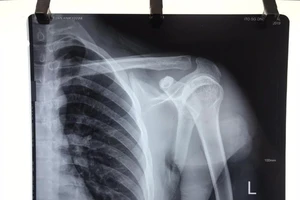

3 giờ vi phẫu nối dây thần kinh cứu cánh tay cho chàng trai